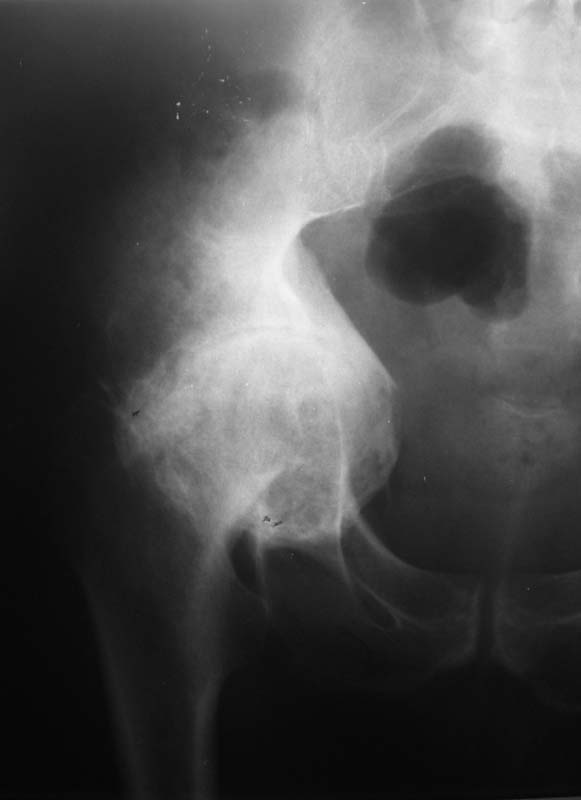

Мужчина, 54 г. В 12 лет перенес травму правого тазоберенного сустава.

Клинически движений в суставе нет, хотя при ходьбе беспокоят боли.

Предполагаем имплантацию <чашки> протеза в сформированное ложе без удаления головки бедра.

Ваше решение абсолютно адекватное и возражений нет, но проблема будет не в этом. У Вас будут сложности в 1) правильной ориентации чашки относительно истинной вертлужной впадины и 2) создании необходимого

"оффсета", попросту говоря, будет крайне сложно "оторвать" бедро от таза. Для этого мы в своей практике пользуемся расширенным передним и задним релизом, как правило, на это уходит достаточно много времени.

Безусловно будут большие технические проблемы с отделением бедра от таза. Ложе для чашки (кстати, какого типа?)придется формировать с нуля. Восстановить длину конечности - тоже проблема, учитывая атрофию окружающих мыщц. Кстати, каково укорочение конечности? В общем, можно получить весь букет технических трудностей протезирования и при этом не получить ни одного его преимущества... Мне кажется, это случай для артродеза.